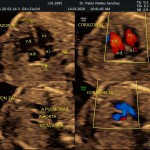

- Las estructuras anatómicas fetales: esta es la mejor etapa del embarazo para el diagnóstico de Malformaciones Estructurales (sensibilidad del 92% aprox.).

- Rastreo de alteraciones cromosómicas (sensibilidad del 60% aprox.).

- El escenario Gravídico: Placenta, liquido, Cérvix y Anexos.